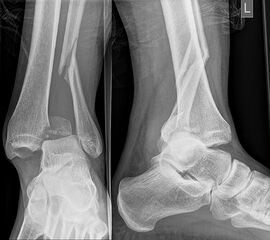

Die Standard-Röntgenaufnahmen des oberen Sprunggelenks bestehen aus drei Aufnahmen: der antero-posterioren Aufnahme (ap), der antero-posterioren Aufnahme mit Innenrotation des Unterschenkels von 20° („Mortise view“), sowie der streng seitlichen Aufnahme (siehe S2-Leitlinie Sprunggelenksfraktur). In der Röntgen-Bildgebung sollte neben den klassischen Frakturzeichen die Integrität der Syndesmose beurteilt werden. Dies erfolgt über die Beurteilung der Breite des lateralen und medialen Gelenkspalts („medial clear space“), des tibiofibularen Abstands 1cm oberhalb des OSG-Gelenkspalts („tibiofibular clear space“), bzw. der tibiofibularen Überlappung. Eine Verbreiterung des tibiofibularen Abstands über 5 mm oder die Erweiterung des medialen Gelenkspalts können Zeichen einer begleitenden Syndesmosenverletzung sein. (Abbildung 3) 6.

Liegt eine Fraktur des oberen Sprunggelenks vor, ist sowohl zur Entscheidung für ein konservatives oder operatives Vorgehen, als auch zur Operationsplanung, ein ausreichendes Verständnis der Fraktur und ihrer Morphologie notwendig. Insbesondere bei komplexen Verletzungen ist dafür die konventionelle Röntgenaufnahme in vielen Fällen nicht ausreichend. So konnten z.B. Black et al. zeigen, dass die operative Strategie zur Versorgung von OSG-Frakturen in 24% basierend auf einer zusätzlichen CT-Bildgebung relevant geändert wurden 7. Dies betraf die Lagerung, die Wahl des Zuganges und die Art der osteosynthetischen Versorgung. Besonders häufig änderte sich das Vorgehen bei Verletzungen des medialen (21%) und des posterioren Malleolus (15%). Darüber hinaus führten dislozierte (dislozierte Frakturen 31% vs. nicht-dislozierte Frakturen 20%) oder komplexe Frakturen (Trimalleolar-Frakturen 29% vs. Unimalleolar-Frakturen 10%) besonders häufig zu relevanten Änderungen des operativen Vorgehens. Die Computertomographie ist daher, insbesondere bei Bi- und Trimalleolar-Frakturen, essentiell für das Verständnis der Fraktur und somit für die Planung und Durchführung der Operation. In Abbildung 4 und 5 sind exemplarisch ein Röntgen- und ein CT Befund gegenübergestellt.